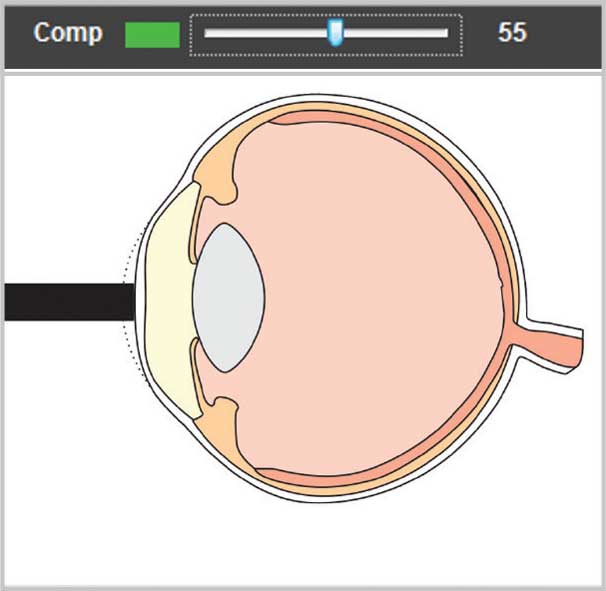

Unique compression lockout feature for use during contact measurements. When enabled, compression lockout will stop the system from measuring waveforms which show indications of corneal compression. Audible tones are provided to guide the user in adjusting contact pressure and aid in alleviating flattening of the cornea. The compression sensitivity level is adjustable to aid in obtaining contact measurements with minimum compression.